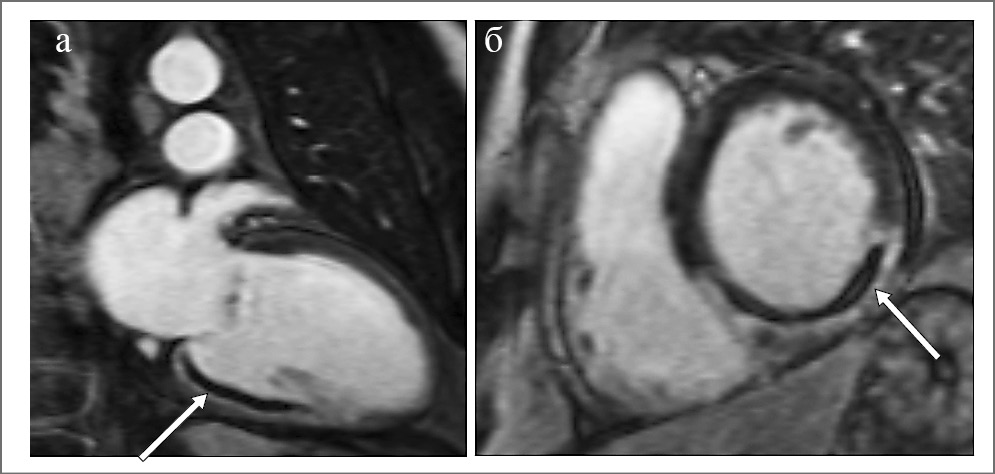

Изображения с отсроченным контрастированием (рис. 4) получают через 10–20 мин после введения гадолинийсодержащего контрастного вещества в дозировке 0,1–0,2 ммоль/кг массы тела больного.

Основными параметрами, которые оцениваются в фазу отсроченного контрастирования у больных с острым ИМпST, являются размер инфаркта, гетерогенность зоны, наличие и выраженность МСО, ИМК.

Размер инфаркта определяется как объем (или масса) зоны острого очагового повреждения (а в последующем фиброза), накапливающей контрастное вещество. Зона инфаркта является морфологически неоднородной. В ее структуру входит ядро, представленное в остром периоде ИМ некротизированными кардиомиоцитами, а в последующем – фиброзной тканью, и гетерогенная зона, состоящая из некротизированных, находящихся в состоянии ишемии и интактных кардиомиоцитов [18–20]. Результаты электрофизиологических исследований и гистологического анализа гетерогенной зоны показали одновременное сосуществование в этой зоне процессов апоптоза и активной репарации [18]. На изображениях МРТ с отсроченным контрастированием гетерогенная зона представляет собой область, где ИС составляет менее 50% от максимальной ИС в зоне инфаркта, но больше максимальной ИС интактной зоны (рис. 4, 5).

Рис. 4. МРТ с отсроченным контрастированием: а – 2-камерная длинная ось ЛЖ; б – 2-камерная короткая ось ЛЖ. Зона накопления контрастного препарата выглядит яркой, низкоинтенсивная область внутри зоны накопления (указано стрелкой) – участок внутрисосудистой обструкции

Результатом нарушения коронарной микроциркуляции в бассейне инфарктсвязанной артерии, даже несмотря на восстановление кровотока, может стать МСО. Патофизиологическим механизмом МСО является вазоконстрикция микроциркуляторного русла в сочетании с дистальной эмболизацией элементами атеросклеротической бляшки, частицами фибрина, тромбоцитов и эритроцитов [21]. На МР-изображениях МСО определяется как темное (гипоинтенсивное) ядро внутри накопивших контрастный препарат участков с высокой ИС, как в фазу раннего контрастирования с гадолинием (ранняя МСО), так и в фазу отсроченного контрастирования (поздняя МСО); рис. 4.